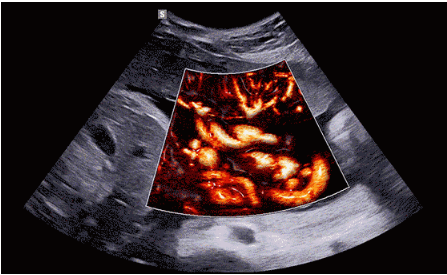

CrystalLive?是三星最新的超聲成像引擎,同時(shí)增強(qiáng)了2D圖像處理能力、3D渲染能力和彩色信號(hào)處理能力,能夠在復(fù)雜情況下提供出色的圖像性能,具備檢測(cè)外周血管、微循環(huán)血流的能力。